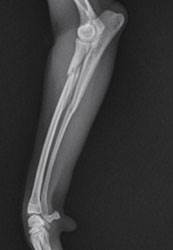

Большинство переломов у домашних животных требуют хирургической стабилизации – операция, которая служит для соединения отломков кости, называется остеосинтез.

Закрепление костных отломков осуществляется при помощи различных фиксаторов – внутрикостных штифтов, пластин, закрепляемых винтами, аппаратов внешней фиксации (спицы или аппарат Илизарова), проволочного серкляжа или сочетания этих методов.

Главная задача операции – обеспечить стабильную фиксацию костных отломков друг относительно друга в анатомически верном положении, и неподвижность зоны перелома до наступления полного сращения.

Хирургический метод лечения (остеосинтез)

у животных является наиболее эффективным и применяется наиболее часто, так как у собак и кошек практически отсутствует возможность использования таких методов консервативного (безоперационного) лечения, как скелетное вытяжение и крайне ограничено применение гипсовых повязок и других иммобилизационных приспособлений.

В зависимости от расположения и типа фиксатора различают внутренний (погружной) остеосинтез (накостный, внутрикостный, чрескостный) и наружный чрескожный (метод Илизарова) и его модификации. Выбор метода хирургического лечения перелома определяет ветеринарный врач исходя из особенностей травмы, сложности перелома, индивидуальных особенностей животного (размер, возраст, состояние костной ткани, темперамент).